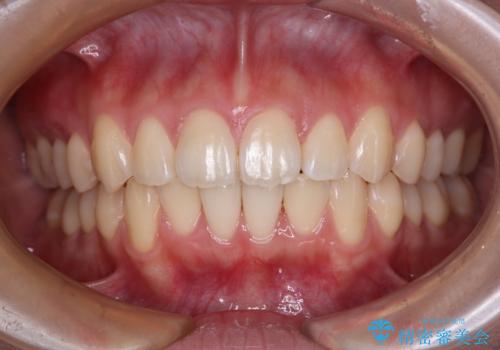

デコボコをワイヤー装置で改善 短期間で綺麗な仕上がりに

1年弱の短期間で、望み通りのスッキリとした口元に仕上げることができました。